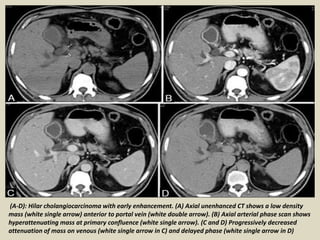

(A-D): Hilar cholangiocarcinoma with early enhancement. (A) Axial unenhanced CT shows a low density

mass (white single arrow) anterior to portal vein (white double arrow). (B) Axial arterial phase scan shows

hyperattenuating mass at primary confluence (white single arrow). (C and D) Progressively decreased

attenuation of mass on venous (white single arrow in C) and delayed phase (white single arrow in D)

(A-D): Hilar cholangiocarcinomawith early enhancement. (A) Axial unenhanced CT shows a low density mass (white single arrow) anterior to portal vein (white double arrow). (B) Axial arterial phase scan shows hyperattenuating mass at primary confluence (white single arrow). (C and D) Progressively decreased attenuation of mass on venous (white single arrow in C) and delayed phase (white single arrow in D)